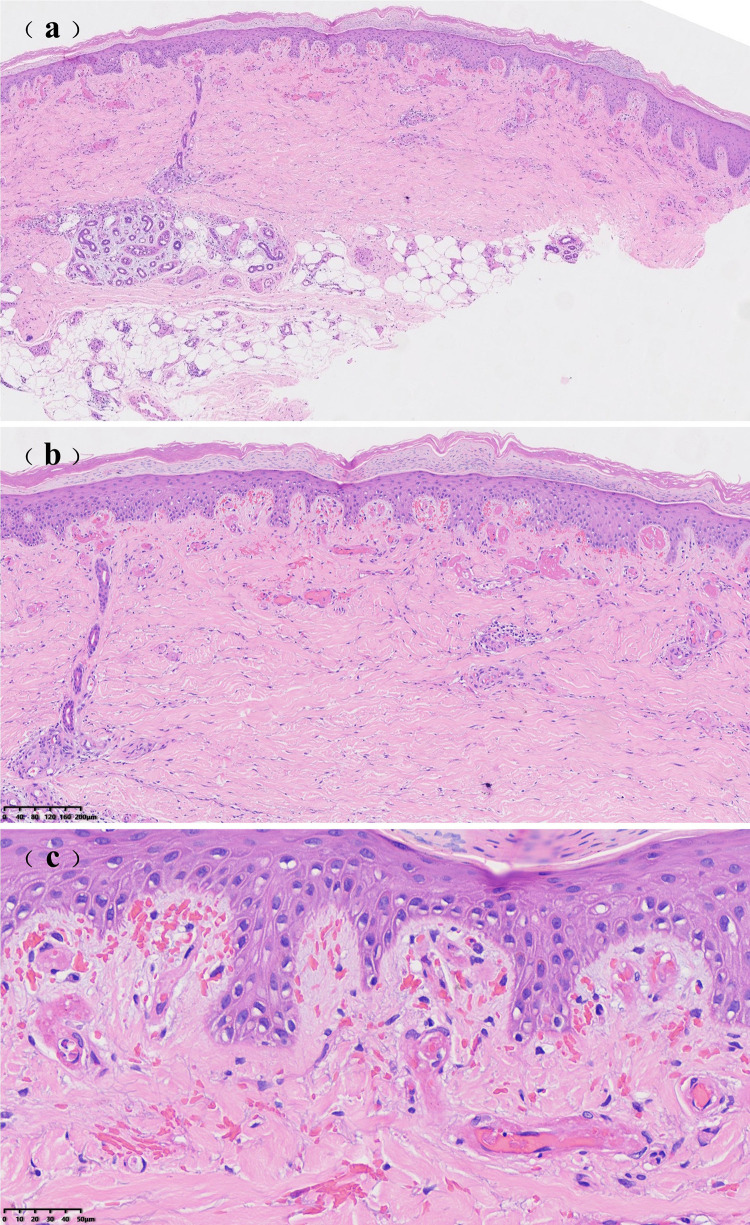

Successful Treatment of Refractory Livedoid Vasculopathy with Upadacitinib: A Case Report.

Purpose: While tofacitinib, baricitinib, and abrocitinib demonstrate efficacy in livedoid vasculopathy (LV), this study evaluates upadacitinib-a distinct Janus kinase (JAK) inhibitor-in refractory LV.

Patients and methods: A 54-year-old female with treatment-resistant LV received upadacitinib (15 mg/day). Treatment response was assessed via composite clinical scores pre- and post-therapy.

Results: Significant improvement occurred within 24 days (score: 7→2), indicating remission. Pain intensity markedly decreased, and near-complete ulcer healing was observed by day 52. No adverse effects were observed, with the exception of orolabial herpes simplex.

Conclusion: Upadacitinib represents a novel therapeutic alternative for LV. Larger cohorts are needed to validate these findings.